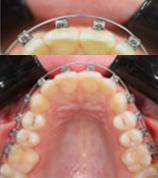

Compensating proclination: Place retrocline brackets on UL2, UL1, UR1, and UR2 to counterbalance the created proclination.

Managing Bolton excess: Address the mandibular Bolton excess by increasing the mesiodistal expression on the upper canines, selecting procline brackets for UL3 and UR3.

Initial leveling in the maxillary arch was carried out with a 0.014 CuNiTi archwire. This was followed by a 0.018 CuNiTi wire, with stoppers positioned mesial to the molars and activated to provide protrusion of incisors. The mandibular arch was then bonded and initial alignment was achieved with a 0.014 CuNiTi wire, then both jaws are progressing to 0.014 × 0.0275 CuNiTi and subsequently 0.018 × 0.0275 CuNiTi for torque control.